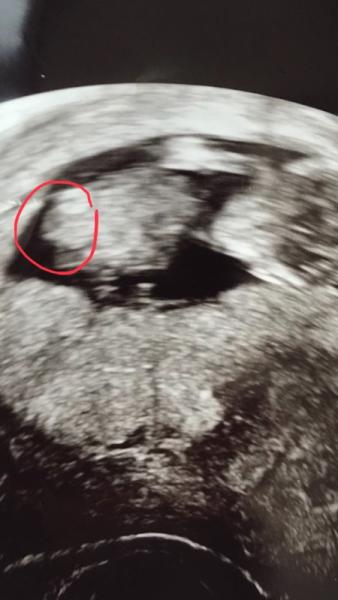

Hmmm glaube da kann man wirklich nur raten Bei uns sah es bei 11+6 ähnlich aus und meine Freundin hat gemeint es wird definitiv ein Junge... aber sie lag daneben ;)

Bild zu

Soweit ich weiss ist das weisse ein Knochen und für mich sieht es aus wie ein Fuß Aber kenne es selber mit dem raten schöne Kugelzeit wünsche ich dir